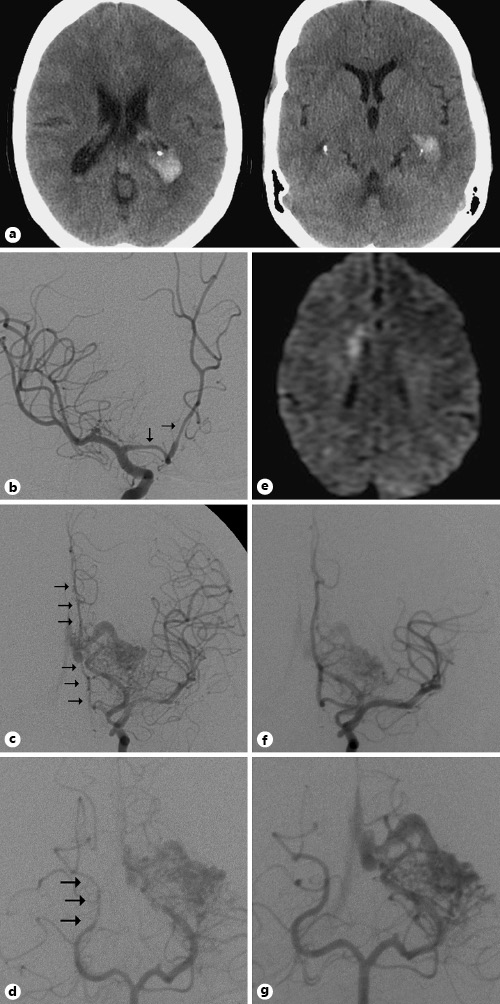

This middle-aged patient presented to the emergency room with severe headache. CT of the head (a) showed an isolated intraventricular hemorrhage within the bilateral lateral ventricles (left greater than right). DSA on postbleed day 7 (b–d) of the bilateral internal carotid arteries and the left vertebral artery shows vasospasm of the proximal right anterior cerebral artery (ACA) (b), the entire left ACA (c), and the P2-P3 segments of the right PCA (arrows) (d). Note the left occipital-temporal region AVM nidus with arterial supply from the left PCA. e MRI on postbleed day 15 shows DWI intensity in the medial right frontal lobe. f, g Follow-up DSA several weeks after the hemorrhage shows resolution of the ACA and PCA vasospasm. The patient underwent successful nBCA embolization and stereotactic radiosurgery of the AVM.